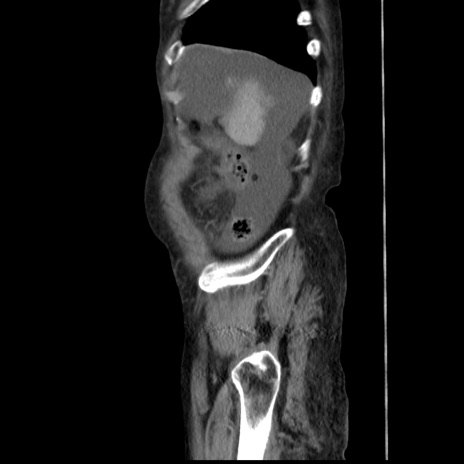

症例31(矢状断像)

【症例】80歳代 女性

【主訴】腹部膨満感

【現病歴】他院にて肝硬変にてフォロー中。1週間前から便秘、腹部膨満感、臍部腫瘤あり受診となる。

【既往歴】肝硬変

【身体所見】腹部膨隆あり、皮膚変化なし、疼痛なし。

【データ】WBC 4600、CRP 0.25